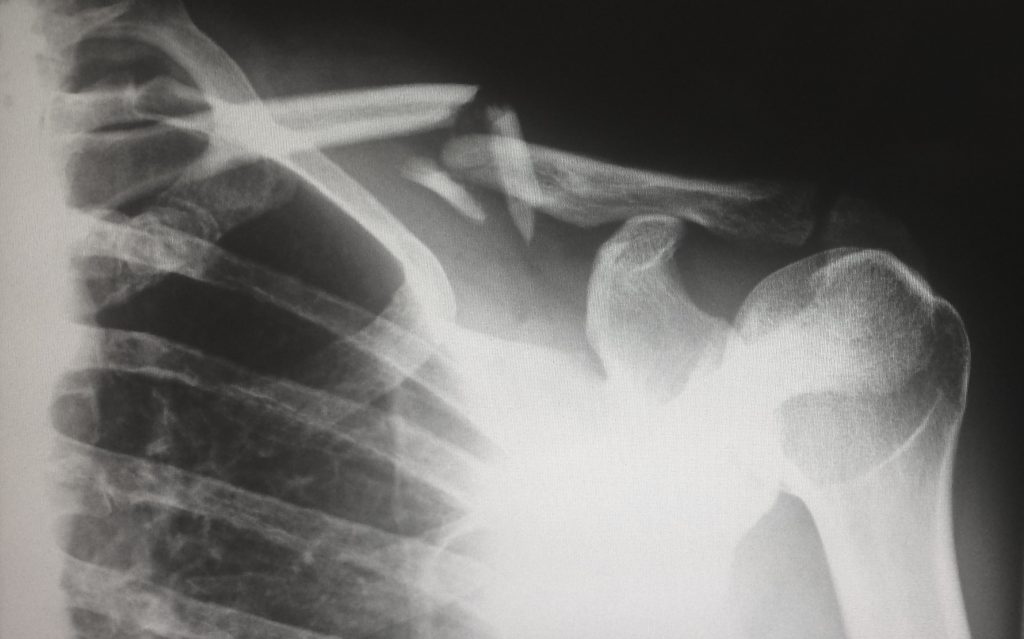

CBD and Broken Bones

Several studies have investigated how CBD can affect bone density. A review of studies in 2018 found that CBD helped bone fractures heal[1]. A different study in 2015 revealed that CBD made bones that were healing from a break stronger which made them harder to break in the future[2]. This is good news as breaking a bone can make it weaker and more likely to be broken again. CBD might be able to help you to recover more effectively from broken bones and get back to your full health as quickly as possible.